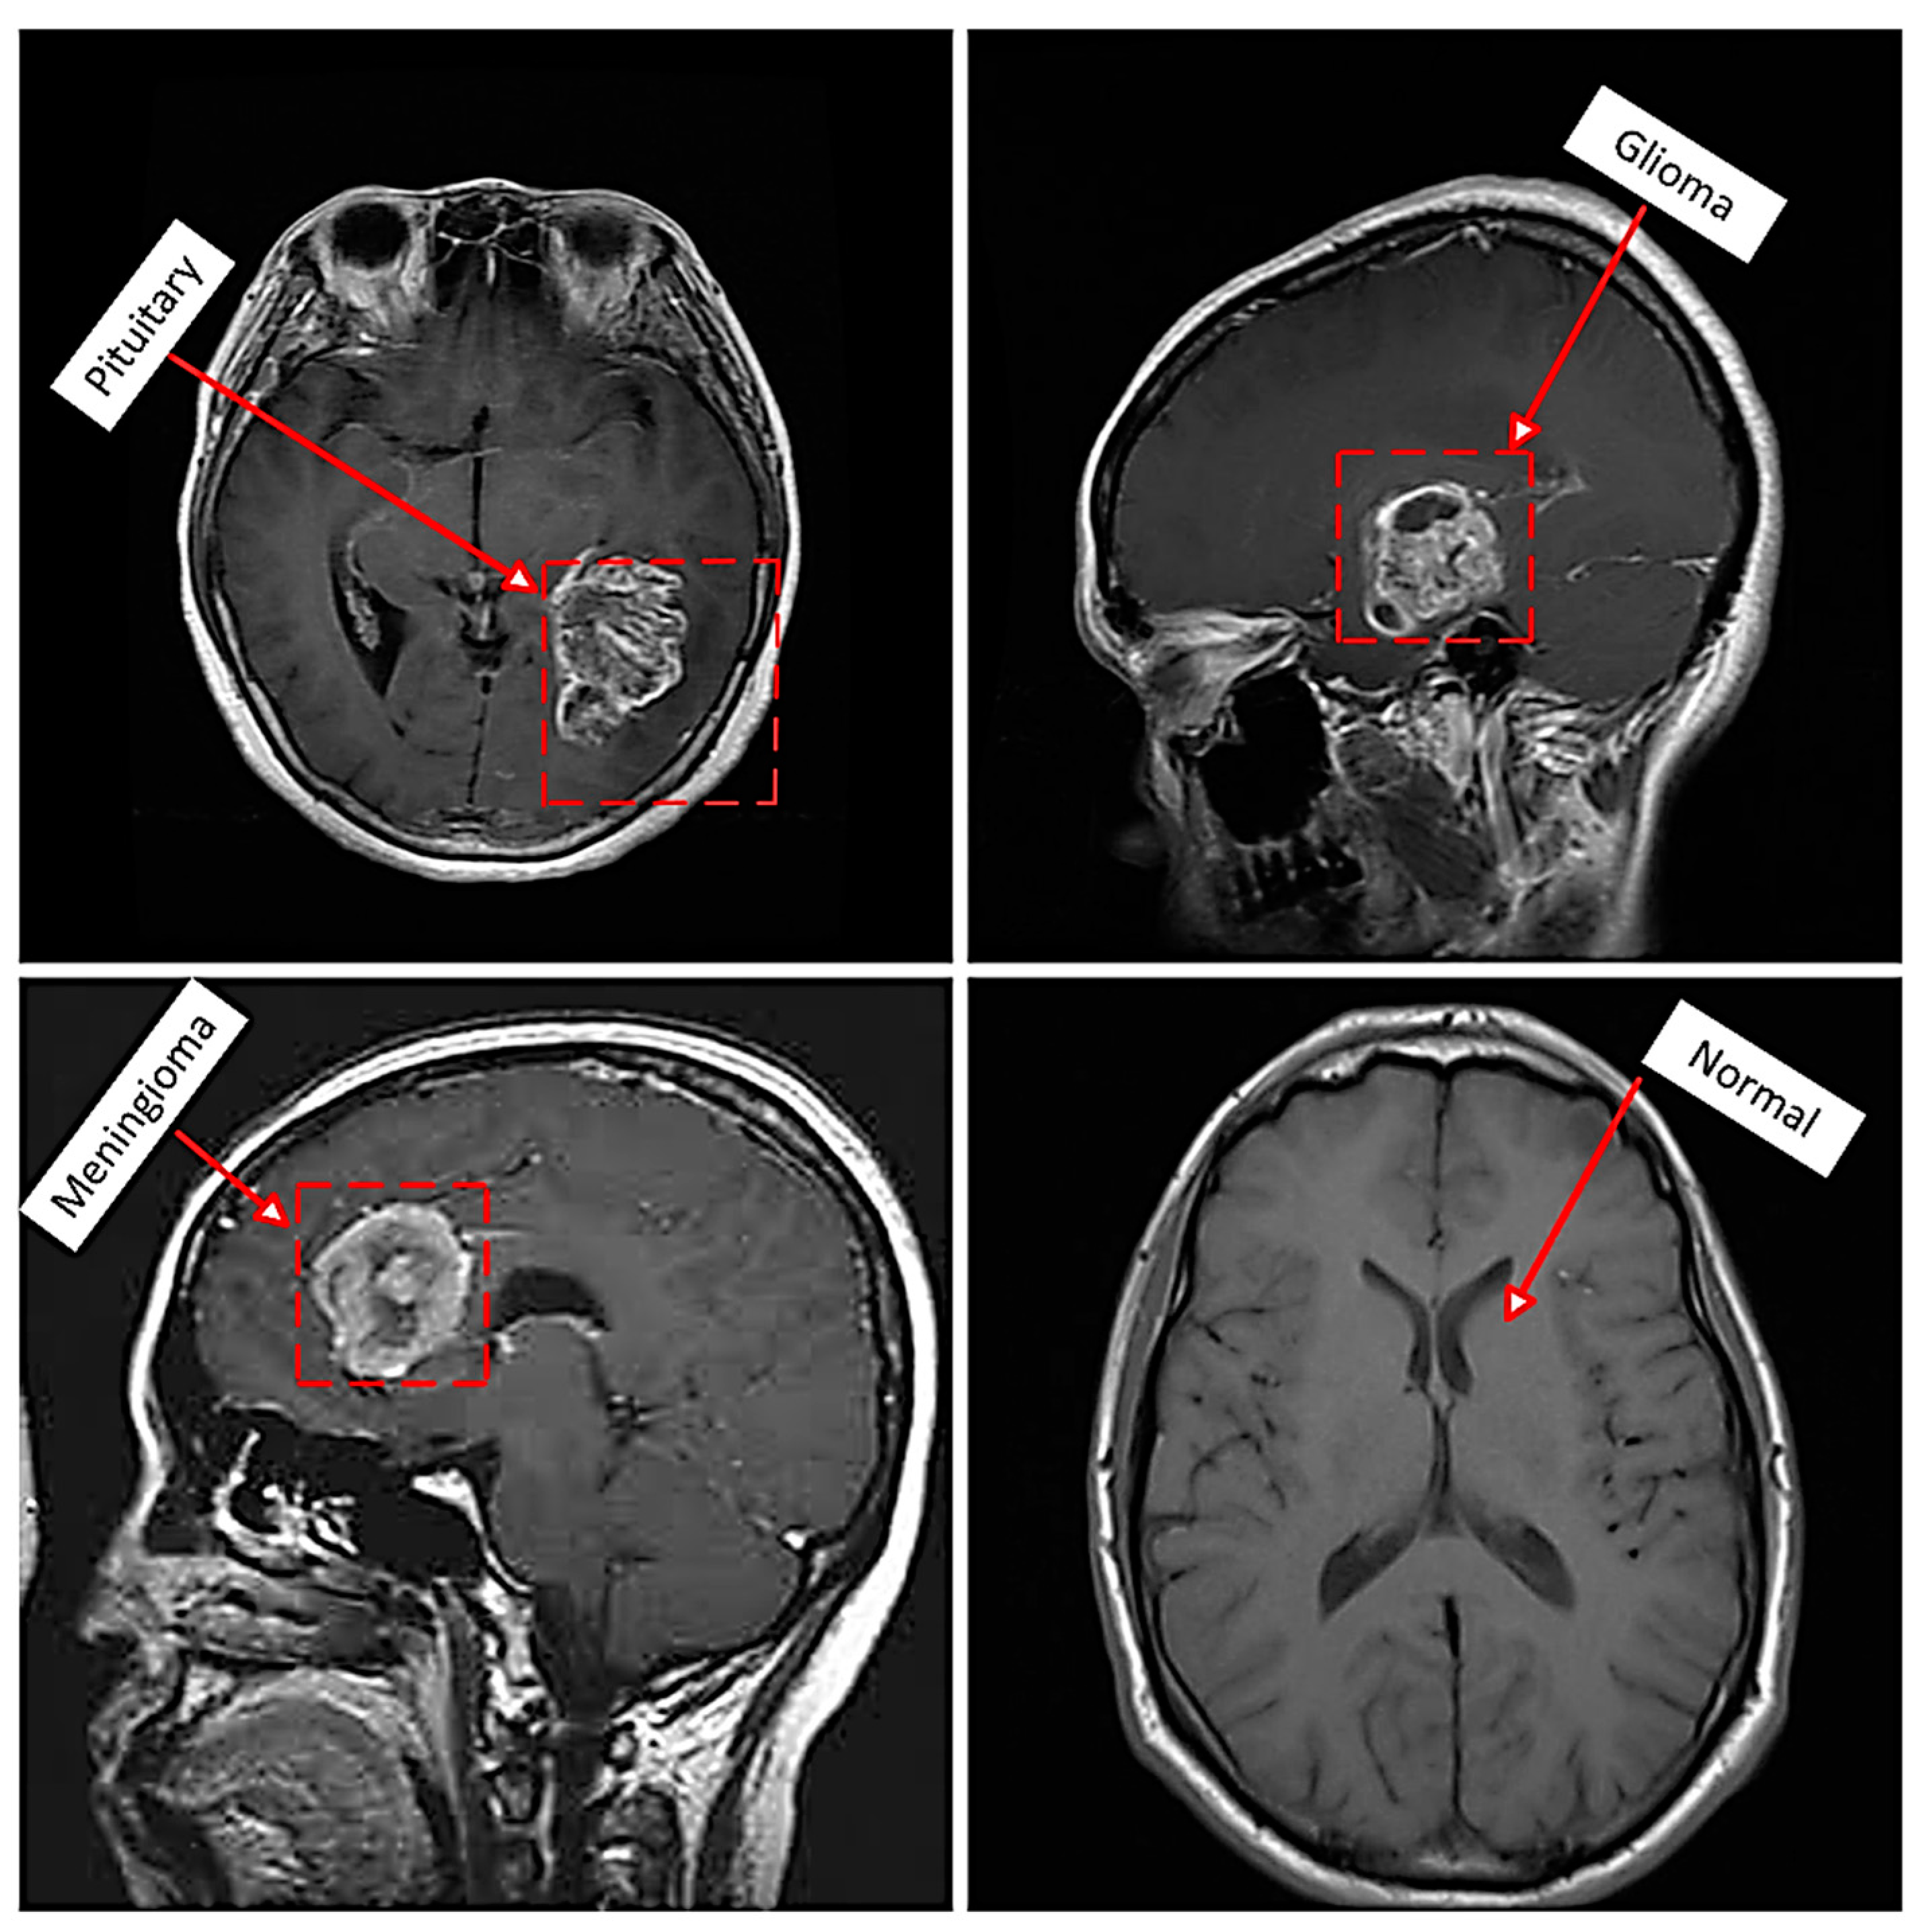

This study validates the effectiveness of the SwT+Resnet50V2 model by evaluating its performance on the Br35H and Kaggle datasets. The Br35H dataset [49] categorizes 3000 images into two groups: normal and tumor. Furthermore, the second dataset contains T1-weighted contrast images of several types of brain tumors [50]. The collection has 926 images categorized as gliomas, 937 as meningiomas, 901 as pituitary tumors, and 396 as normal, as shown in Figure 4. The present research partitions the dataset into three subsets and relies on the following proportion of testing and training data: 80% for training, 10% for validation, and 10% for testing. Table 3 shows the hyperparameter combinations employed to simulate the proposed model using a Python application. ReLU was applied as an activation function, with batch sizes of 32, 25, and 50 epochs, a learning rate of 0.0001, and a dropout rate of 0.5. Initial testing, which systematically evaluated various values to enhance the model’s performance, influenced the selection of these hyperparameters. For instance, we evaluated different learning rates (from 0.001 to 0.00001) and batch sizes (16, 32, and 64), selecting the most effective combination based on validation accuracy and loss. Throughout the training, a learning rate of 0.0001 and a batch size of 32 continuously achieved outstanding convergence, avoiding overfitting and ensuring dependable gradient updates. We selected a dropout rate of 0.5 to regularize the model and prevent overfitting. To avoid overfitting and underfitting, we used epochs of 25 and 50. The ReLU activation function was chosen because it works well for allowing gradient propagation in deep learning applications.

Figure 4. Instances of the types of brain tumor in MRI images.